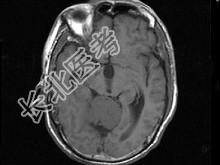

- 单项选择题男,61岁, 头晕头痛伴行走不稳1月余,根据所提供图像, 最可能的诊断是 ( )

A、胶质瘤

B、髓母细胞瘤

C、(天幕切迹缘)脑膜瘤

D、转移瘤

E、淋巴瘤